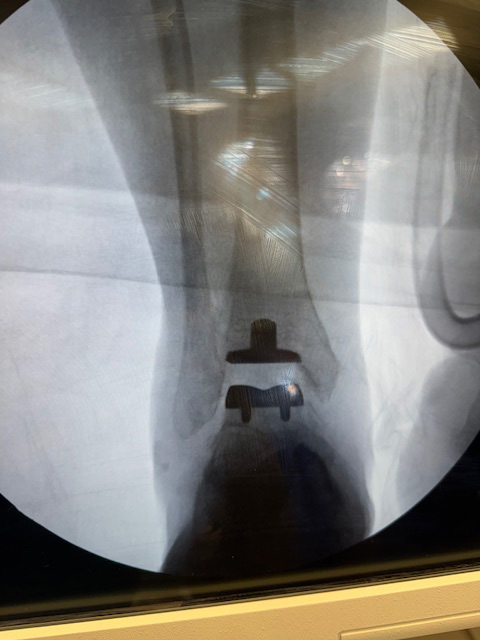

In March 2011 I contracted Necrotizing Fasciitis in my lower left leg/ankle/foot. The infection resulted in the loss of nearly 40% of my ankle bone and limited my range of movement to less than 10% – up/down, no lateral movement what so ever. Also my foot and ankle were in constant pain. I was on a daily regimen of 75mg Tramadol 2x’s daily until the ankle was replaced in January 2014 by Dr. Stoddard.

Dr. Stoddard evaluated my ankle, my desire to increase mobility and reduce the chronic pain. After several consults with other Orthopedics to discuss my ankle and its ‘current’ condition – Frozen bone mass, Dr. Stoddard recommended a total ankle replacement.

Dr. Stoddard discussed the entire procedure with me – Up and downsides – Best case – No pain and good range of movement for the entire foot and ankle – system. Worst case – I’d be a Pirate with a nice Peg-leg on the left side. ‘Spinning’ would NOT be a problem, dancing would be… Luckily the better of the two cases prevailed. I had the total ankle replacement completed by Dr. Stoddard and his team at SOCO. My recovery has been a challenge, (self-inflicted – When the Dr. tells you to do or NOT do something, listen and follow direction.),… a little longer than I had hoped. I am now walking, pain free, I’m still in Physical Therapy, working on range of motion and re-building leg/foot muscle. The recover for me was a little longer than normal or expected due to my past ankle history and infections…and I pushed the process, a little harder than I should have – Hind sight is always 20/20.